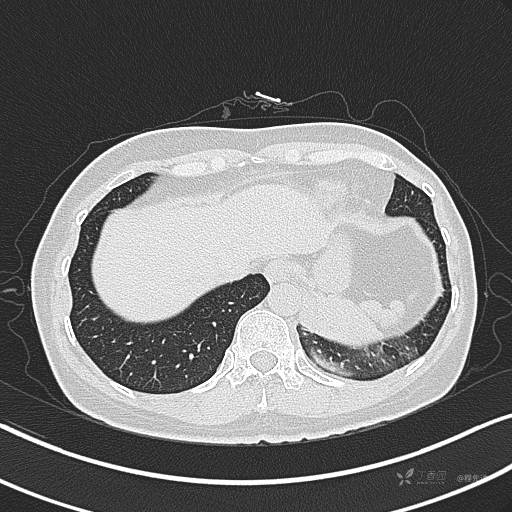

增强静脉期

静脉期CT值约84HU

CT值:平扫:31HU,动脉期:74HU,静脉期:84HU